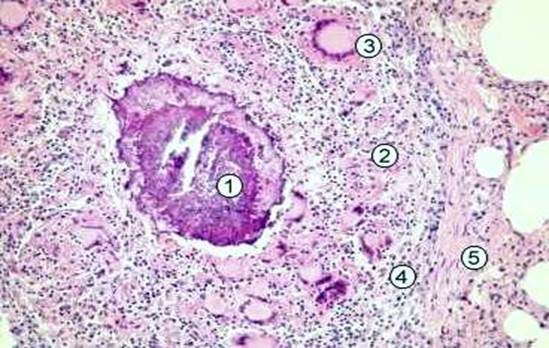

Рис. 31. Милиарная туберкулезная гранулема. В центре расположен участок казеозного некроза с обызвествлением (1 – участок обызвествленного казеозного некроза); 2 – зона эпителиоидных клеток; 3- гигантские клетки Пирогова-Лангханса; 4 – зона лимфоидных клеток, представленная лимфоцитами, плпзмоцитами; 5 – формирующаяся соединительнотканная капсула